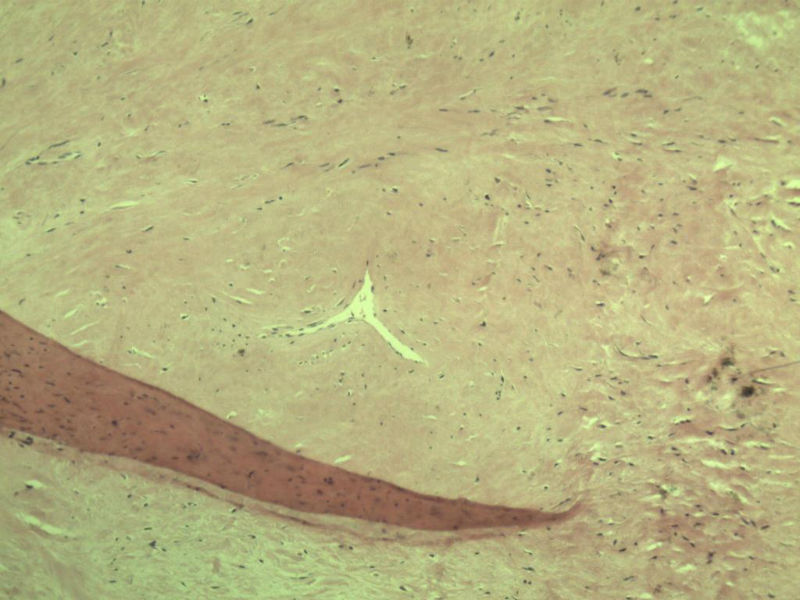

男,51岁, 4月前患者无意中发现右腘窝一包块,约核仁大小无疼痛, 4月来包块进行性生长

灰褐类圆形包块一个,直径 5 cm,切面灰白,实性,编织状。 请各位老师看看 是什么? 谢谢!